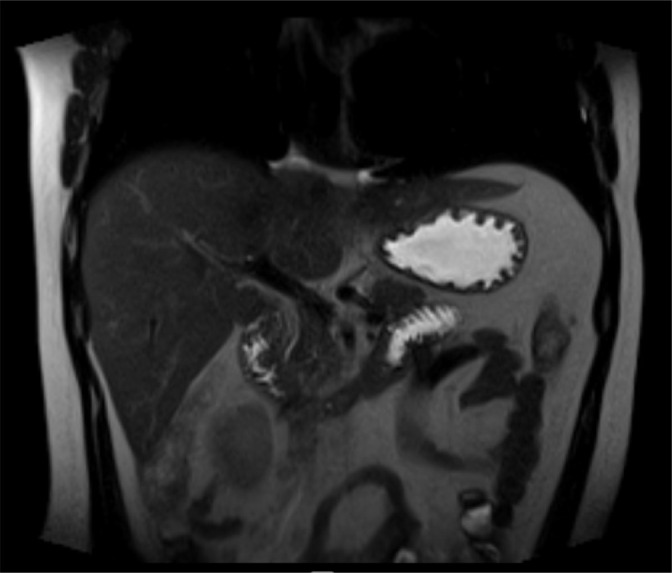

Case report: A 21-year-old male patient presented with intermittent painful crises, located in the upper abdomen, with radiation to the back, associated with nausea and vomiting, for the past three years. Magnetic resonance imaging and endoscopic retrograde cholangiopancreatography revealed pancreas divisum, subsequently confirmed by endoscopic ultrasound. An attempt was made through endoscopic intervention but failed to catheterize the minor papilla; therefore, a pancreaticoduodenectomy was indicated. The organ was identified as hard and atrophied, with moderate peripancreatic inflammation. The histopathological findings also identified a focal well-differentiated G1-type neuroendocrine tumor measuring 0.4 cm.